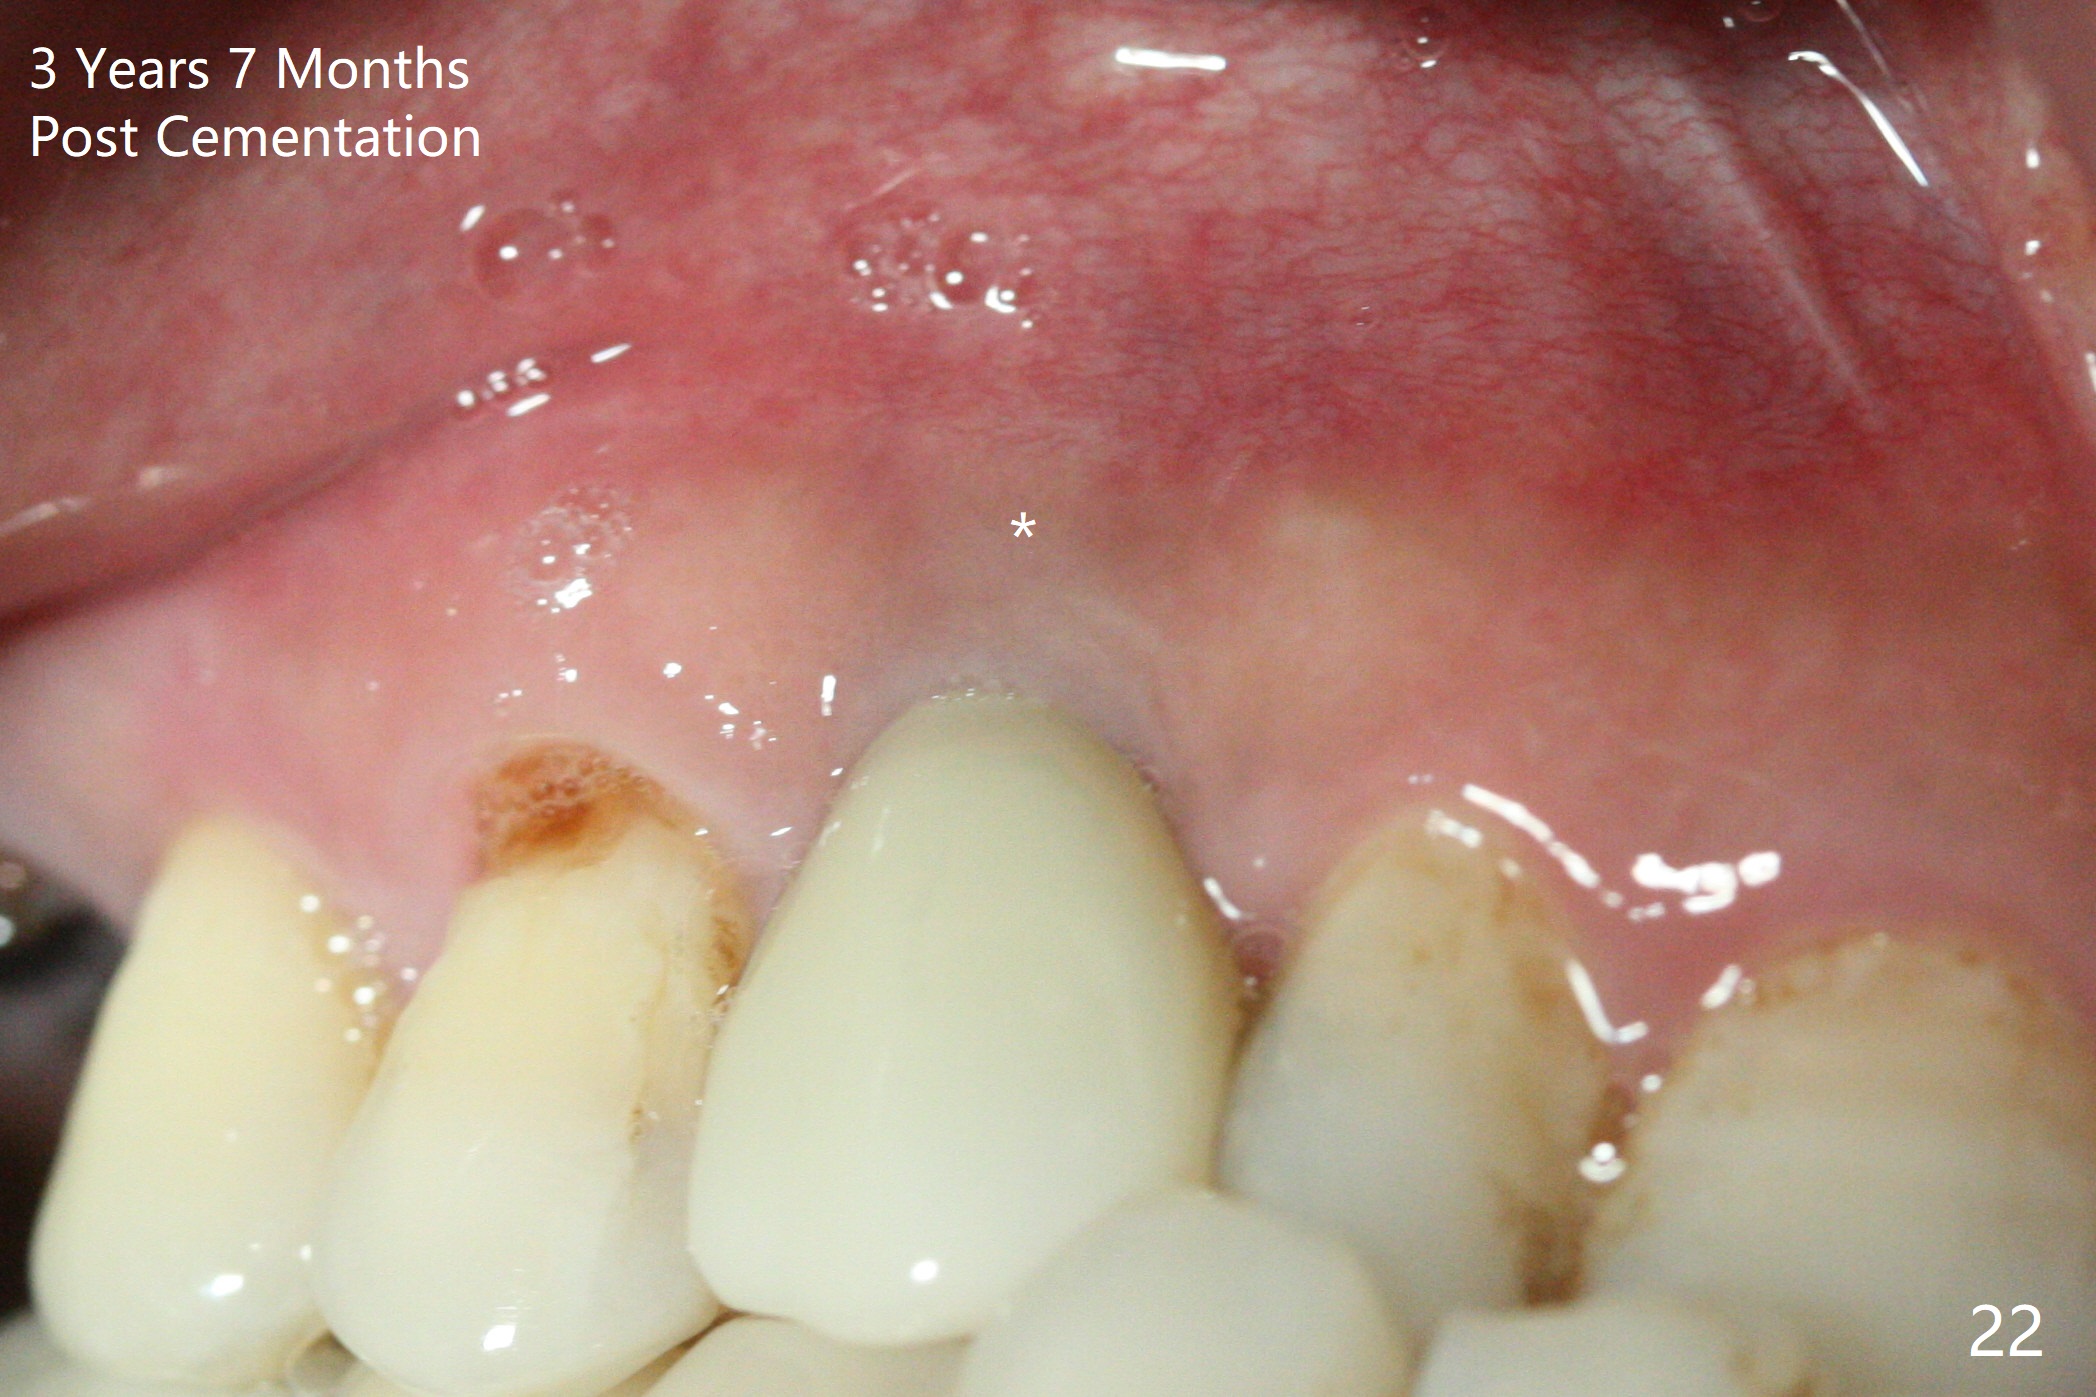

To be improved: 1. Implant could be placed more palatal; 2. Gingival laceration should have been sutured prior to bone grafting; 3. The buccal margin of the provisional should have been extended more buccally to prevent bone graft from dislodgement; the provisional should be relined and recemented securely; 4. More rigid membrane should have been used to keep convexity of the buccal plate. The crestal bone is stable 3 Years 7 Months Post Cementation (Fig.21). The buccal plate is slightly atrophic 3 Years 7 Months Post Cementation (Fig.22).